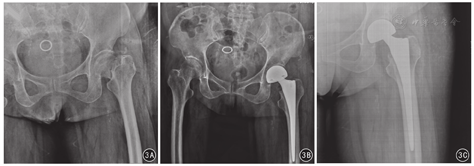

术后19例获随访,随访时间均为3个月。手术后3个月随访门诊观察见19例患者术侧髋关节活动度正常并稳定,无下肢深静脉血栓形成、切口感染、大腿中段疼痛、股骨骨折、坐骨神经损伤等并发症;门诊骨盆前后位X线片见股骨柄假体位于中立位,无股骨柄下沉,无髋关节假体脱位。典型病例见图3。